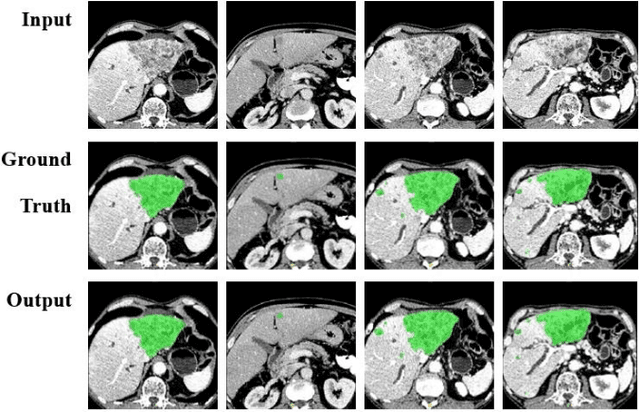

Abstract:Automatic segmentation of liver tumors in medical images is crucial for the computer-aided diagnosis and therapy. It is a challenging task, since the tumors are notoriously small against the background voxels. This paper proposes a new three-stage curriculum learning approach for training deep networks to tackle this small object segmentation problem. The learning in the first stage is performed on the whole input to obtain an initial deep network for tumor segmenta-tion. Then the second stage of learning focuses the strength-ening of tumor specific features by continuing training the network on the tumor patches. Finally, we retrain the net-work on the whole input in the third stage, in order that the tumor specific features and the global context can be inte-grated ideally under the segmentation objective. Benefitting from the proposed learning approach, we only need to em-ploy one single network to segment the tumors directly. We evaluated our approach on the 2017 MICCAI Liver Tumor Segmentation challenge dataset. In the experiments, our approach exhibits significant improvement compared with the commonly used cascaded counterpart.